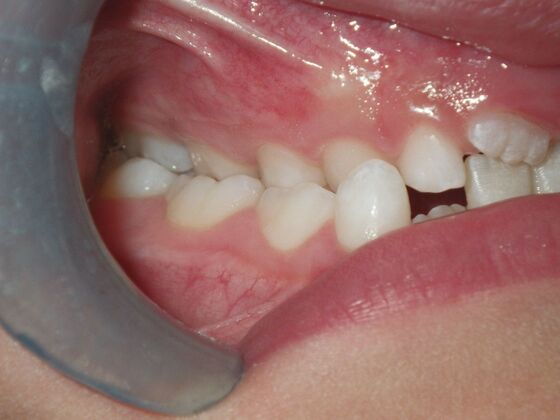

Orthodontic treatment in Phases: Case 8

Description

Dylan presented with a functional crossbite in which we used removable expansion appliances for 12 months, followed by bracketing of upper and lower teeth including primary ones to gain alittle more expansion, allowed to wear retainers for 6 months and then followed closely with 6 month ortho recalls and began Phase 2 treatment within 24 months and finished his ortho treatment.